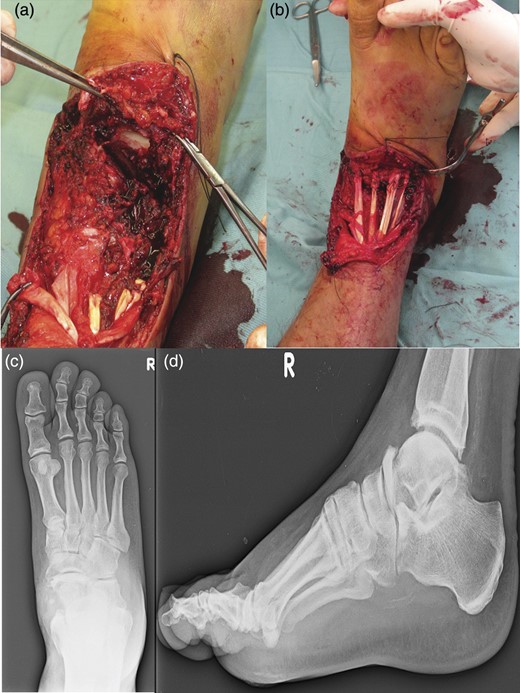

The fixation of the calcaneocuboid joint was carried out using two 4.0-mm cannulated screws. The screws were brought from proximal to distal, starting in the anterior process area and brought obliquely across into the cuboid (Fig. 4).

The placement of an autologous graft into the talonavicular joint harvested from the omolateral iliac crest (a). The fixation of the calcaneocuboid joint was carried out using two 4.0-mm cannulated screws (b) and the talonavicular joint was fused in situ using two 4.0-mm cannulated screws across the talonavicular joint (c).

At the sixth month follow-up, the patient had returned to work and remained pain free while walking, with good fusion of both joints (Fig. 5).

AP (a) and lateral (b) radiographs of the foot in the cast after the surgical time. AP (c) and lateral (d) radiographs of the foot at the sixth month follow-up.